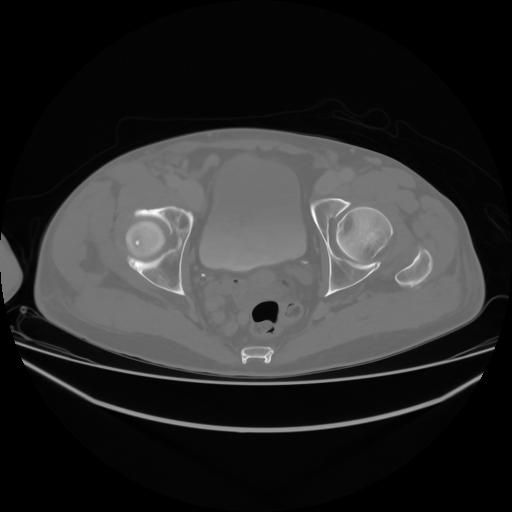

4 CUERPO,CE,Axial,3.0,CUERPO,,